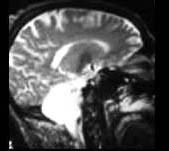

根据图示考虑是何种疾病 ( )A、小脑发育不良B、无脑畸形C、扁平颅底D、Arnold-Chiari畸形E、小脑扁桃体肿瘤

问题 根据图示考虑是何种疾病 ( )

选项 A、小脑发育不良 B、无脑畸形 C、扁平颅底 D、Arnold-Chiari畸形 E、小脑扁桃体肿瘤

答案 A